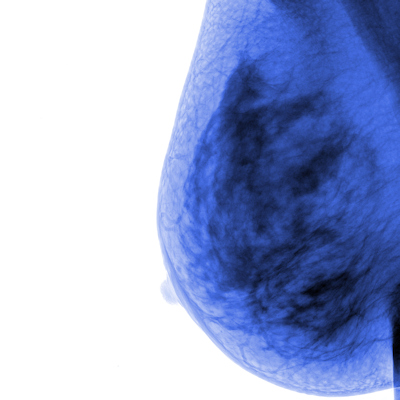

A commercial AI system achieved high marks as a first reader in double-reader settings for breast cancer screening, a Danish study published December 20 in Cancer Imaging found.

Elhakim and co-authors studied the effectiveness of a commercially available AI system (Transpara version 1.7.0, ScreenPoint Medical BV) in a Danish screening population. They assessed the system’s detection accuracy in two scenarios, standalone and integrated screening replacing the first reader. They also compared the results with those of first reading and combined reading.